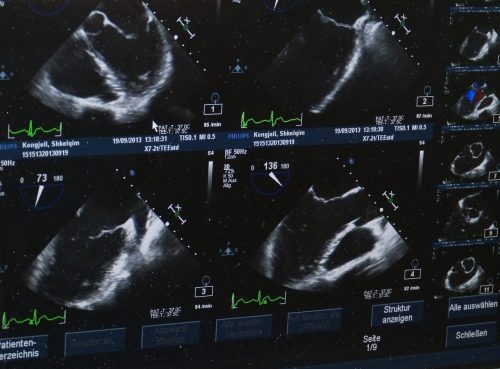

The prevalent use of technology in cosmetic procedures has influenced BBL in many ways. Ultrasound helps surgeons follow the fat transfer process thoroughly with real-time imagery, ensuring the correct placement of the fat away from the gluteal muscle. As discussed in an article on NCBI (2023), Ultrasound guided BBL offers a safer surgery by adding one more cautionary step to it, decreasing the risk of complications and making it more convenient to target the area for fat transfer.

The fat tissue extracted from predetermined areas is then purified and filtrated. In BBL with ultrasound, fat acts as a filler substance, harvested from donor areas. So unwanted fat tissue in one area can be useful to highlight another area, in this case, the buttocks. To begin the fat transfer process, namely lipofilling in Turkey, a wireless ultrasound machine is used, enabling live tracking to determine where to deposit the purified fat. This new technological approach makes it easier for the specialist to inject the fat into the correct layer of the skin, which is above the muscle. These attentively determined areas for fat deposit increase precision and minimizes the risk of complications, through injection into the right layer of soft tissue.